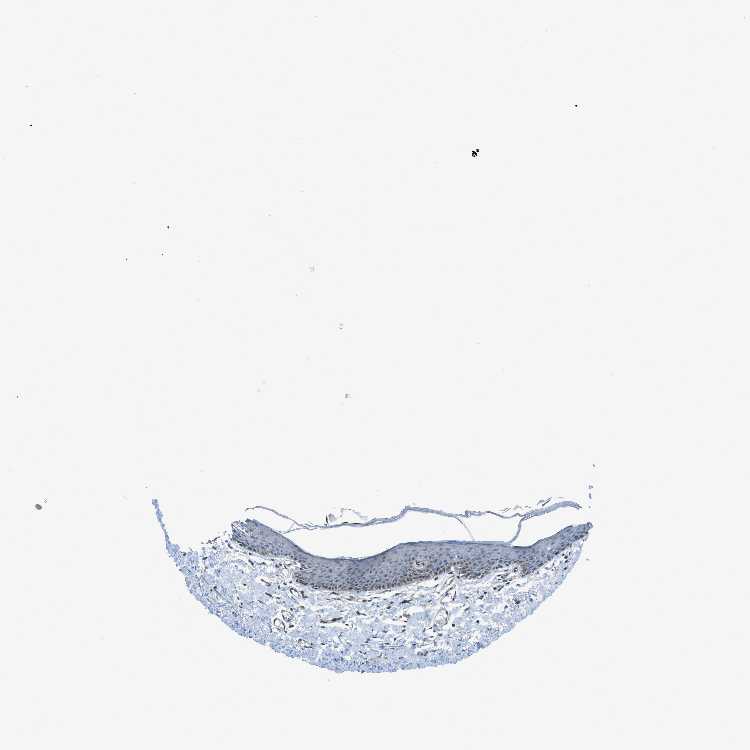

SKIN 1 - Antibody stainingi

Antibody staining in the annotated cell types in the current human tissue is reported as not detected, low, medium, or high, based on conventional immunohistochemistry profiling in selected tissues. This score is based on the combination of the staining intensity and fraction of stained cells.

Each image is clickable and will lead to virtual microscopy that enables deeper exploration of all samples and also displays staining intensity scores, fraction scores and subcellular localization as well as patient and tissue information for each sample.

Antibody HPA036012Antibody CAB016257

Langerhans MediumNot detected

Fibroblasts LowNot detected

Keratinocytes Not detectedNot detected

Melanocytes LowNot detected

SKIN 2 - Antibody stainingi

Epidermal cells LowNot detected